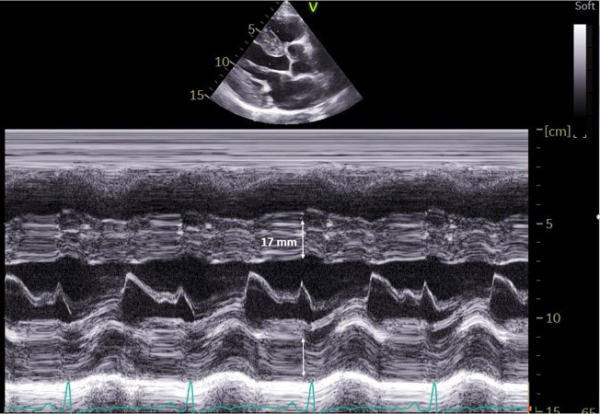

L’échographie cardiaque montre:

- Hypertrophie circonférentielle de 17 mm (Figure 6)

- Dilatation à 44 mm du sinus de Valsalva

Figure 6 : Mode TM – coupe parasternale grand axe